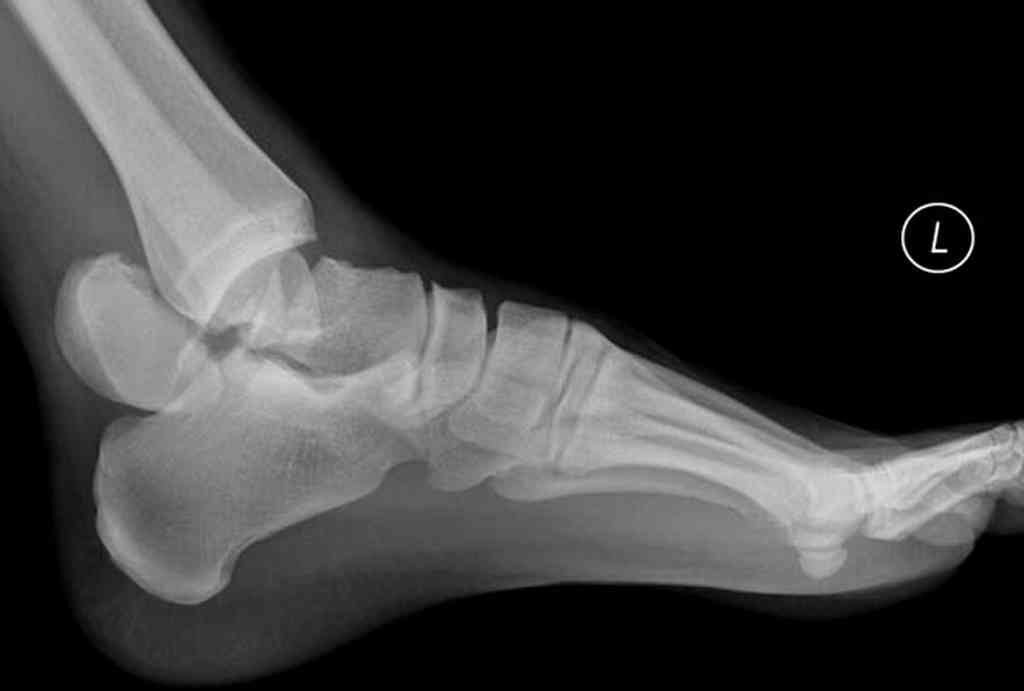

Переломовывих тарана с повреждением медиальной стороны. Через 4 часа после поступления проведена репозиция и фиксация тарана после Irrigation&Debridment. Частичное несращение медиальной лодыжки не беспокоит, вернулся к активному образу жизни. Полная нагрузка разрешена через 11 недель. Финальные снимки через 11 месяцев.